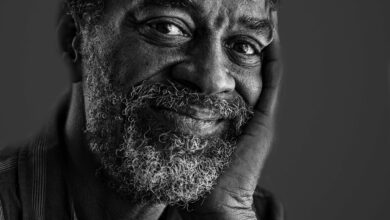

Declínio cognitivo subjetivo associado a maior risco de demência para pessoas negras e latinas

Crédito: Pixabay/CC0 Domínio Público Algumas pessoas relatam um declínio em sua memória antes que qualquer declínio seja grande o suficiente…